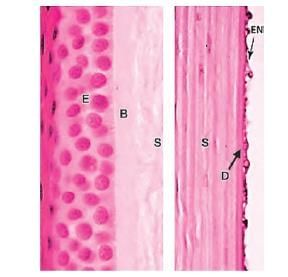

Which layer maintains hydration of corneal stroma? (NEET-PG 2020p)

Identify the marked layer in the given histological section: (AIIMS Nov 2019)